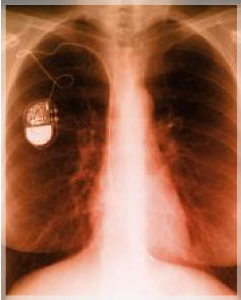

A aquellos pacientes cuyo número de pulsaciones es insuficiente para cubrir las demandas circulatorias de nuestro cuerpo. En la actualidad los marcapasos estimulan tanto atrios como ventrículos (las cavidades del corazón) lográndose un funcionamiento más fisiológico; además los que aumentan su frecuecnia de pulsaciones según la demanda del organismo, como por ejemplo, durante el ejercicio físico y muchas otras funciones que se programan según las necesidades de cada paciente.¿A quienes se les coloca un cardiodesfibrilador implantable?

Este dispositivo que se parece a un marcapasos, realiza además otras funciones; se implanta en personas que han tenido un paro cardiaco y han sido existosamente recuperadas. También a quienes no hayan sufrido este tipo de evento, pero que se presuma que exista un alto riesgo de padecerlo.¿Qué es un estudio electrofisiológico?